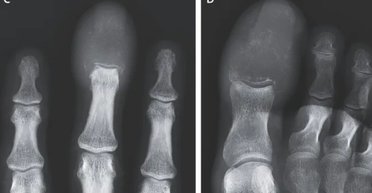

У чоловіка з'явився болючий набряк середнього пальця на правій руці та великого пальця на правій нозі. Лікарі з'ясували, що незвичайний набряк пальців виявився рідкісною ознакою раку, що поширився по тілу пацієнта.